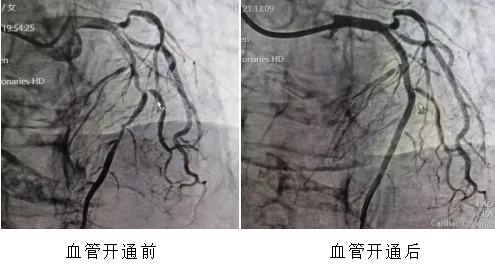

这不是一组普通的时间记录,而是一个真实的、发生在海南医科大学第一附属医院导管室的急救故事——前不久的一天,12小时内,通过胸痛中心绿色通道,5位急性心肌梗死患者,5台急诊经皮冠状动脉介入治疗(PCI)手术,全部成功。

急性心肌梗死,意味着给心脏供血的血管被血栓堵死。每延误一分钟,就有大量心肌细胞不可逆地坏死。此时,时间就是生命。从当天19点到次日清晨,导管室的门开合了5次。每一次,都是一位素不相识的患者把生命托付给这群穿着铅衣的人。

22分钟、70分钟、36分钟、18分钟、12分钟——这是5颗心脏血管从“断流”到“复流”,解除堵塞病变的时间。如此高密度、高效率的连续急救,绝非偶然,它是我院胸痛中心标准化、流程化救治能力的集中体现。它的背后,是院前院内无缝联动,120急救车上已完成的心电图传输与初步诊断,患者“未到,信息已到”,导管室提前启动;是术前早已启动的医院胸痛中心绿色通道——患者到我院后可绕行ccu和(或)急诊科,直接进入导管室,最大限度压缩术前准备时间;更是心内科、急诊科、心电图室、导管室护理团队等多学科团队的无缝咬合,高效协作。这是急诊急救体系建设的力量。